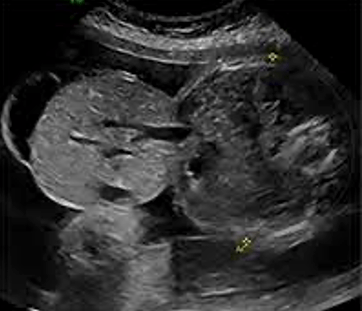

What is this condition?

Cystic hygroma

Also accepted: Thickened nuchal translucency